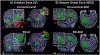

Figures